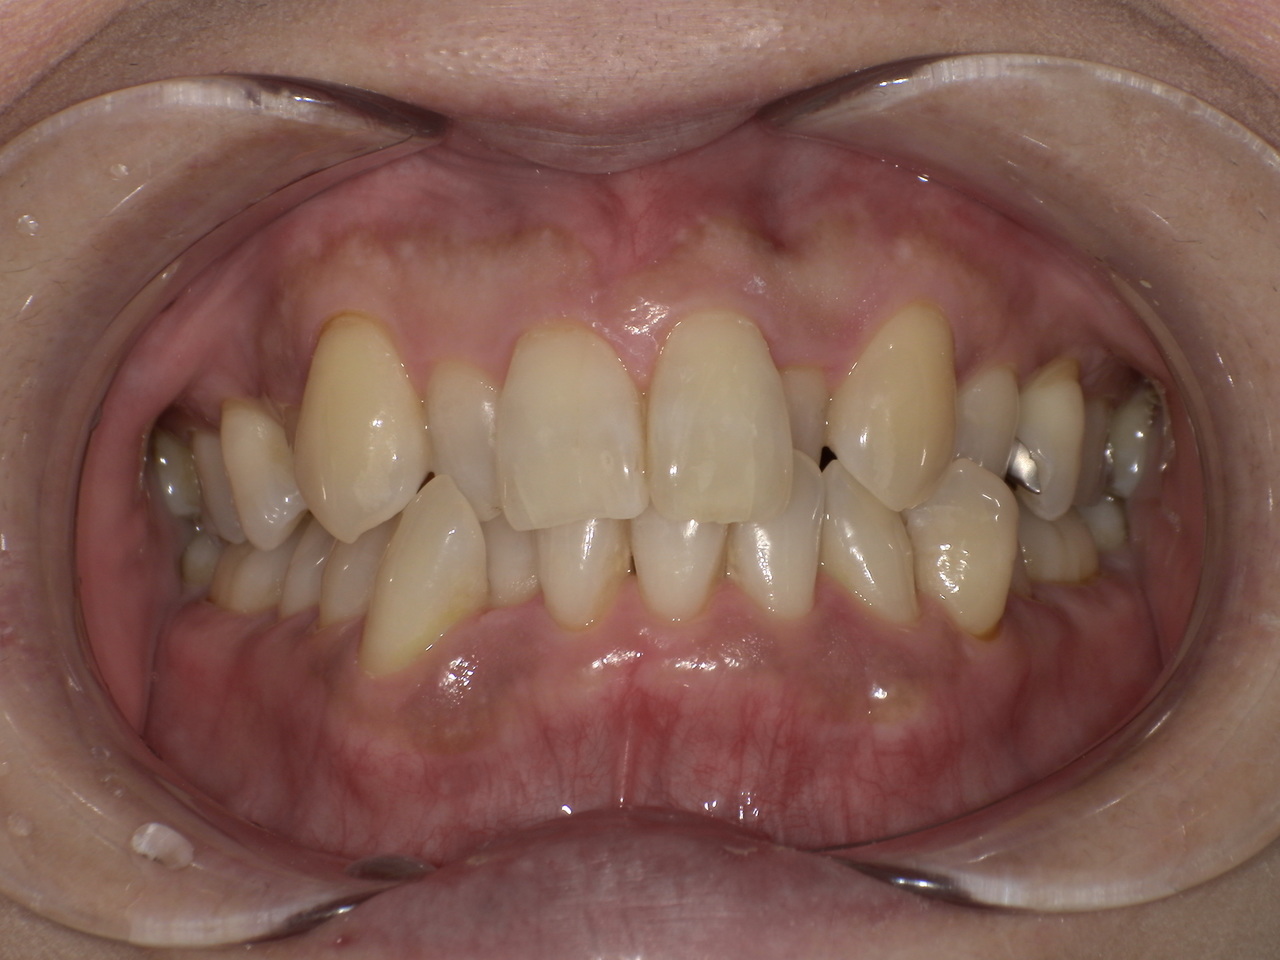

ステイン除去

BEFORE

AFTER

年齢:20代男性

治療内容:エアーフローによる歯の着色汚れ、ステイン除去

治療期間/通院回数:1回

費用: ステインコース 8,800円

リスク・副作用

①効果には個人差があり、着色汚れによっては一度に取りきれない場合があります。

施術後数時間以内に、着色効果の強いもの(コーヒー・紅茶・喫煙など)を摂取すると、歯に色素沈着が起こる可能性があります。

パウダーの刺激により歯ぐきから出血する可能性があります(痛みはほとんどありません)。